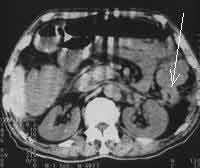

В 10-ти случаях выявлены признаки характерные для рака ободочной кишки: неравномерное утолщение стенок ободочной кишки от 1,0 до 2,6см, нечеткость контуров, повышение плотности окружающей клетчатки, уплотнение переднего листка околопочечной фасции (в случаях рака восходящей и нисходящей кишок) (Рис. 1- 4). В 2-х случаях рак ободочной кишки сопровождался  признаками кишечной непроходимости (Рис. 5). В одном случае массивная опухоль исходила из правой почки и вовлекала восходящую кишку. В другом — выявлена опухоль имеющая неоднородную мягкотканную плотность, относительно четкие контуры расположенная, премущественно экстраорганно по отношению к нисходящей кишке (Рис. 6). В одном случае при пероральном контрастировании ободочной кишки создалось впечатление ракового поражения селезеночного угла толстой кишки, для уточнения исследование повторили после очистительной клизмы и раздувания — в результате выявлен полип на ножке (Рис. 7). При обследовании постоперационных больных — в 1-м случае выявлен околоободочный абсцесс, в другом — явления анастомозита после левосторонней гемиколонэктомии, проявляющегося утолщением стенок кишки в зоне анастомоза до 6мм с выраженным расширением проксимальной части кишки. В двух случаях при КТ исследовании не получено убедительных данных за опухолевое поражение ободочной кишки хотя данные колоноскопии указывали на раковое заболевание или малигнизированный полип.

Рис. 3. Рак поперечноободочной кишки: локальное утолщение задней стенки кишки вблизи печеночного изгиба (стрелки), наличие увеличенных до 1,1 см лимфоузлов вблизи измененной кишки.